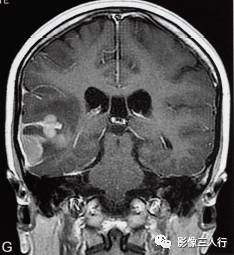

图1右颞叶横纹肌样脑膜瘤

A.T1WI横断面;B、C.T2WI横断面;D、E、F、G.增强横断面、矢状面、冠状面;H.HE×100

图1A:MRI T1WI示,右侧颞叶不规则形肿块,信号欠均匀,为稍低信号与小斑片状稍高信号混杂。其累及颞叶灰白质,界限欠清、边缘不整,大小约4.1cm×4.3cm×5.1cm。邻近脑沟脑裂变浅变平,周边脑实质受压。图1B、C:T2WI示,右颞不规则形肿块,信号欠均匀,为稍高信号与小斑片状略低信号混杂。灶周见带状高信号脑水肿。图1D~G:T1WI C示,右侧颞叶肿块呈不均匀的多个结节块状明显强化,邻近脑膜为线条状强化、增厚。